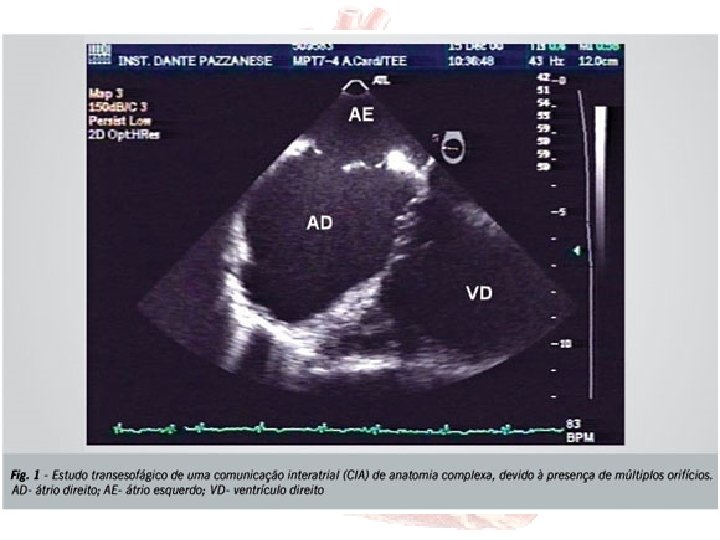

ECOCARDIOGRAFIA • • • Método de escolha Sensibilidade 70 a 100% - CIA Tipo e tamanho Direções dos shunts Função VD (movimento paradoxal do septo) Pressão - artéria pulmonar

TRATAMENTO PERCUT NEO • • CIA secundum Diâmetro < 36 mm Bordas adequadas Percutâneo – Fluoroscopia e ETE – Eco intracardíaco • Indicações = • critérios de seleção com particularidades